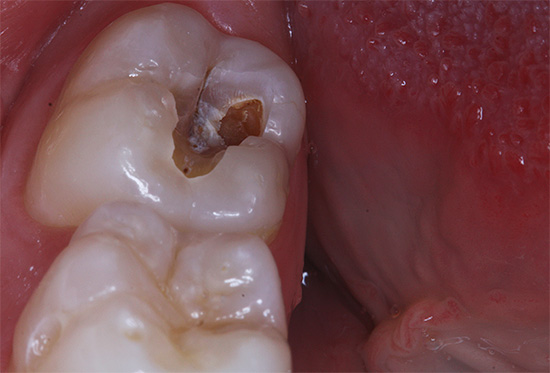

La foto sotto mostra un esempio di carie profonde, in cui la camera pulpare del dente è già molto probabilmente interessata:

Carie acuta profonda caratterizzato da dolore a breve termine da una varietà di sostanze irritanti. Spesso la cavità ha un ingresso profondo e stretto con una base larga. Se potessi raschiare le pareti di una tale cavità con qualcosa di solido (e i dentisti lo fanno regolarmente ai ricevimenti), noteresti che la dentina infetta e pigmentata ammorbidita si separa sempre abbondantemente dalle pareti della cavità.

La seguente foto mostra un esempio di una cavità così profonda e cariata: